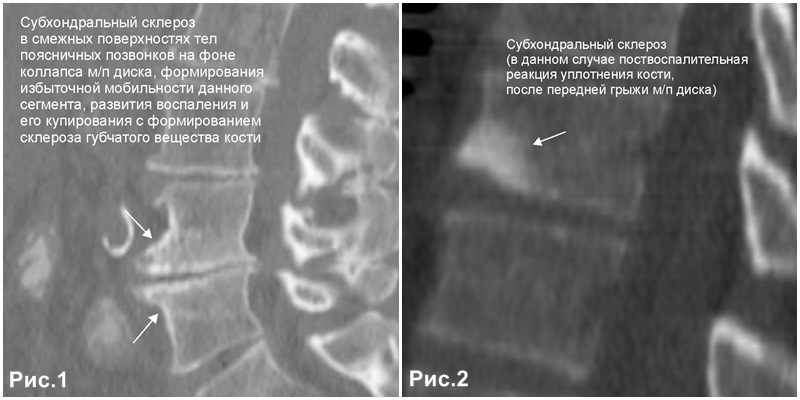

Рентгеновские снимки остеосклероза костной ткани